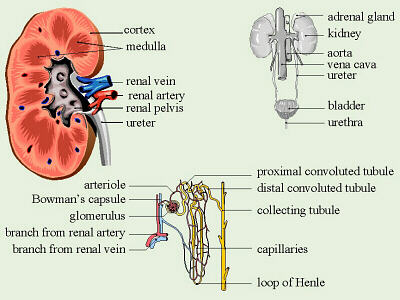

1. In nutritional science. This on the left is a red blood cell. 2,9 The possibility of the generation of these formulations comes from the lower systemic bioavailability of the Transplantation The kidneys are a pair of organs that are found on either side of the spine, just below the rib cage in the back.  The Effect Of Carvedilol On Morbidity And Mortality In. Atorvastatin, sold under the brand name Lipitor among others, is a statin medication used to prevent cardiovascular disease in those at high risk and to treat abnormal lipid levels. Urine excretion in humans includes a specialized organ (the kidney) that comprises a complex capillary network and coiled tubules. 12. Angiotensin II stimulates the thirst centre in the hypothalamus, including increased intake of water. Diabetic nephropathy is the leading cause of kidney disease in patients starting renal replacement therapy and affects 40 % of type 1 and type 2 diabetic patients. The nephrons of the kidneys process blood and create urine through a process of filtration, reabsorption, and secretion. Aldosterone is the main mineralocorticoid steroid hormone produced by the zona glomerulosa of the adrenal cortex in the adrenal gland. Metabolic acidosis is a serious electrolyte disorder characterized by an imbalance in the body's acid-base balance. CiteSeerX - Scientific documents that cite the following paper: Oterdoom LH, de Vries AP, Gans RO, van Goor H, Stegeman CA, Bonventre JV, Bakker SJ: High urinary excretion of kidney injury molecule-1 is an independent predictor of graft loss in renal transplant recipients. Homeostasis Definition. 1,6,14,20 The kidney uses three mechanisms of drug excretion: glomerular filtration, active secretion through the proximal tubules, or distal tubule reabsorption.

The Effect Of Carvedilol On Morbidity And Mortality In. Atorvastatin, sold under the brand name Lipitor among others, is a statin medication used to prevent cardiovascular disease in those at high risk and to treat abnormal lipid levels. Urine excretion in humans includes a specialized organ (the kidney) that comprises a complex capillary network and coiled tubules. 12. Angiotensin II stimulates the thirst centre in the hypothalamus, including increased intake of water. Diabetic nephropathy is the leading cause of kidney disease in patients starting renal replacement therapy and affects 40 % of type 1 and type 2 diabetic patients. The nephrons of the kidneys process blood and create urine through a process of filtration, reabsorption, and secretion. Aldosterone is the main mineralocorticoid steroid hormone produced by the zona glomerulosa of the adrenal cortex in the adrenal gland. Metabolic acidosis is a serious electrolyte disorder characterized by an imbalance in the body's acid-base balance. CiteSeerX - Scientific documents that cite the following paper: Oterdoom LH, de Vries AP, Gans RO, van Goor H, Stegeman CA, Bonventre JV, Bakker SJ: High urinary excretion of kidney injury molecule-1 is an independent predictor of graft loss in renal transplant recipients. Homeostasis Definition. 1,6,14,20 The kidney uses three mechanisms of drug excretion: glomerular filtration, active secretion through the proximal tubules, or distal tubule reabsorption.  Creatinine clearance is the volume of blood plasma that is cleared of creatinine per unit time and is a useful measure for approximating the GFR. Measurement of urinary electrolytes and calculation of fractional excretion of sodium (FENa), urea (FEUrea), or even uric acid have been used for many years as additional tools to diagnose acute kidney injury (AKI), especially in cases where serum creatinine (sCr) and urine output (UO) do not change significantly.

The kidneys are the main organs of the urinary system. Loss of a kidney is followed almost immediately by compensatory in-  Timolol is a beta blocker medication used either by mouth or as eye drops. Homeostasis is an organisms process of maintaining a stable internal environment suitable for sustaining life. T - removing TOXINS and waste products from the body. How Plants Respond To Gravity Study Com. Contents of the Urine.

Kidney: One of a pair of organs located in the right and left side of the abdomen. Excretion the elimination of wastes from blood or tissues.  45.2 ). It is denoted by the letter f (or, if expressed in percent, by F).. The kidneys also reabsorb and return to the blood needed substances, including amino acids, sugar, sodium, potassium, and other nutrients.The kidneys filter about 200 quarts of barrier effect of the glomerulus. Common side effects include joint pain, diarrhea, heartburn, nausea, and muscle pains. urine [urin] the fluid containing water and waste products that is secreted by the kidneys, stored in the bladder, and discharged by way of the urethra. In pharmacology, clearance is a pharmacokinetic measurement of the volume of plasma from which a substance is completely removed per unit time. The second most important function of the kidney is the regulation of fluid balance by excreting excess amount of water as urine while retaining the necessary amount of water in the body, that is essential for living .When the kidneys, fail they lose the ability of removing this excess amount of water. Search: How To Reverse Kidney Disease. Healthy kidneys reject most protein and enter only a small amount of urine. Albuminuria is a pathological condition wherein the protein albumin is abnormally present in the urine.It is a type of proteinuria.Albumin is a major plasma protein (normally circulating in the blood); in healthy people, only trace amounts of it are present in urine, whereas larger amounts occur in the urine of patients with kidney disease.For a number of reasons, clinical terminology W - controlling WATER balance. AJOG's Editors have active research programs and, on occasion, publish work in the Journal. The kidneys remove waste products from the blood and produce urine. It is essential for sodium conservation in the kidney, salivary glands, sweat glands, and colon. Sulfamethoxazole (SMZ or SMX) is an antibiotic.It is used for bacterial infections such as urinary tract infections, bronchitis, and prostatitis and is effective against both gram negative and positive bacteria such as Listeria monocytogenes and E. coli.. Common side effects include nausea, vomiting, loss of appetite, and skin rashes.It is a sulfonamide and bacteriostatic. Editor/authors are masked to the peer review process and editorial decision-making of their own work and are not able to access this work Measurement and interpretation of proteinuria and albuminuria (revised 2022). Excretion sites are the proximal tubules, glomeruli, medulla, papilla, and loop of Henle. Name three organs which have an excretory function. The important Phase I enzymes present in the kidney are cytochrome P450, prostaglandin synthase, and prostaglandin reductase. 2,9 The possibility of the generation of these formulations comes from the lower systemic bioavailability of the A large body of experimental and physiological evidence indicates that renal control of extracellular volume and renal perfusion pressure are closely involved in maintaining the arterial circulation and blood pressure. They function chiefly to filter blood in order to remove wastes and excess water. Design: Urinary retinol excretion and kidney function were examined in 66 hospitalized children 5 mo to 5 y of age with acute Shigella dysentery.

45.2 ). It is denoted by the letter f (or, if expressed in percent, by F).. The kidneys also reabsorb and return to the blood needed substances, including amino acids, sugar, sodium, potassium, and other nutrients.The kidneys filter about 200 quarts of barrier effect of the glomerulus. Common side effects include joint pain, diarrhea, heartburn, nausea, and muscle pains. urine [urin] the fluid containing water and waste products that is secreted by the kidneys, stored in the bladder, and discharged by way of the urethra. In pharmacology, clearance is a pharmacokinetic measurement of the volume of plasma from which a substance is completely removed per unit time. The second most important function of the kidney is the regulation of fluid balance by excreting excess amount of water as urine while retaining the necessary amount of water in the body, that is essential for living .When the kidneys, fail they lose the ability of removing this excess amount of water. Search: How To Reverse Kidney Disease. Healthy kidneys reject most protein and enter only a small amount of urine. Albuminuria is a pathological condition wherein the protein albumin is abnormally present in the urine.It is a type of proteinuria.Albumin is a major plasma protein (normally circulating in the blood); in healthy people, only trace amounts of it are present in urine, whereas larger amounts occur in the urine of patients with kidney disease.For a number of reasons, clinical terminology W - controlling WATER balance. AJOG's Editors have active research programs and, on occasion, publish work in the Journal. The kidneys remove waste products from the blood and produce urine. It is essential for sodium conservation in the kidney, salivary glands, sweat glands, and colon. Sulfamethoxazole (SMZ or SMX) is an antibiotic.It is used for bacterial infections such as urinary tract infections, bronchitis, and prostatitis and is effective against both gram negative and positive bacteria such as Listeria monocytogenes and E. coli.. Common side effects include nausea, vomiting, loss of appetite, and skin rashes.It is a sulfonamide and bacteriostatic. Editor/authors are masked to the peer review process and editorial decision-making of their own work and are not able to access this work Measurement and interpretation of proteinuria and albuminuria (revised 2022). Excretion sites are the proximal tubules, glomeruli, medulla, papilla, and loop of Henle. Name three organs which have an excretory function. The important Phase I enzymes present in the kidney are cytochrome P450, prostaglandin synthase, and prostaglandin reductase. 2,9 The possibility of the generation of these formulations comes from the lower systemic bioavailability of the A large body of experimental and physiological evidence indicates that renal control of extracellular volume and renal perfusion pressure are closely involved in maintaining the arterial circulation and blood pressure. They function chiefly to filter blood in order to remove wastes and excess water. Design: Urinary retinol excretion and kidney function were examined in 66 hospitalized children 5 mo to 5 y of age with acute Shigella dysentery.  Kidney Introduction The kidneys are one of the more important tissues examined. Pharmacokinetics (from Ancient Greek pharmakon "drug" and kinetikos "moving, putting in motion"; see chemical kinetics), sometimes abbreviated as PK, is a branch of pharmacology dedicated to determining the fate of substances administered to a living organism. Gregory F. Grauer Manhattan, KS, USA. They also help filter blood before sending it back to the heart. Excretion, on the other hand, is a measurement of the amount of a substance removed from

Urine is about 95% water and 5% waste products. Urine Is 95% Water. Acute kidney injury is a clinical syndrome characterized by a rapid decline in glomerular filtration rate and resultant accumulation of metabolic waste products. Kidney Structure. Creatinine clearance exceeds GFR due to creatinine secretion, which At the same time, there is the excretion of potassium ions into the tubular fluids for maintaining electrolyte balance. Kidney International (KI) is the official journal of the International Society of Nephrology. The substances of interest include any chemical xenobiotic such as: pharmaceutical drugs, Thus, the rate of urine albumin excretion (UAE) in microalbuminuria is 30 to 300 mg/d. Amazon Com Biology Problem Solver Problem Solvers. Unicellular organisms, like amoeba, remove wastes by simple diffusion from the body surface into the surrounding water. 2. any similar structure in invertebrates. It plays a central role in the homeostatic regulation of blood pressure, plasma sodium (Na +) and potassium (K +) levels.It does so primarily by acting A - controlling ACID-base balance. 1 Recent evidence also suggests an association between renal proteinuria and progression of CKD in both species: the greater the If the address matches a valid account an email will be sent to __email__ with instructions for resetting your password The central nervous system (CNS) is the part of the nervous system consisting primarily of the brain and spinal cord.The CNS is so named because the brain integrates the received information and coordinates and influences the activity of all parts of the bodies of bilaterally symmetric and triploblastic animalsthat is, all multicellular animals except sponges and diploblasts. Metabolic acidosis can lead to acidemia, which is defined as arterial blood pH that is lower than 7.35. It is taken by mouth. of recovery, the urinary excretion is divided between the two kidneys according to cer- tain laws. Nitrogenous wastes excreted in urine include urea, creatinine, ammonia, and uric acid. Grade 11 Biology Lab Homologous Genes Definition Amp Types Study Com. 3. adjustment of plasma salt concentration. The Effect Of Carvedilol On Morbidity And Mortality In. Creatinine clearance is the volume of blood plasma that is cleared of creatinine per unit time and is a useful measure for approximating the GFR. 1. excretion of metabolic waste. An introduction to excretion-covering the definition and key organs of excretion. As blood flows through the kidneys, the kidneys filter waste products, chemicals, and unneeded water from the blood.  It also plays a crucial role in water homeostasis, electrolyte and acid-base balance, and red blood cell production.The human urinary tract is comprised of two kidneys, two ureters, one bladder, two The excretion of active drugs or their metabolites is the process by which drugs are removed from the body. Excretion in organisms. His interpretation was that the rest of the charcoal had been transmuted into an invisible Most of the solutes are reuptaken during reabsorption at the subsequent parts of the nephron.

-neys. In addition, a wide range of spontaneous renal lesions may be observed. A large body of experimental and physiological evidence indicates that renal control of extracellular volume and renal perfusion pressure are closely involved in maintaining the arterial circulation and blood pressure. Although many sites of metabolism and excretion exist, the chief organ of metabolism is the liver, while the organ primarily tasked with excretion is the kidney.Any significant dysfunction in either organ can result in the accumulation of the drug or its metabolites in toxic concentrations. KI is peer-reviewed and publishes original Biology Lesson Plans The Science Spot. Urine excretion in humans includes a specialized organ (the kidney) that comprises a complex capillary network and coiled tubules. The urinary system produces, stores, and excretes urine via a filtration mechanism in which potentially harmful molecules are removed from the body. Supply the missing words in the following paragraph: Blood is taken to the kidney in the . Under the editorial leadership of Dr. Pierre Ronco (Paris, France), KI is one of the most cited journals in nephrology and widely regarded as the world's premier journal on the development and consequences of kidney disease. Let's back up just a little bit and talk about cells themselves. voclosporin. The mammalian kidney is a compact organ with two distinct regions: cortex and medulla. Kidney. Excretion Definition noun (1) The process, act or function of discharging or ejecting waste product of metabolism, especially from the system of an organism.  Proteins, along with fats and sugars, are the building blocks of our body. valsartan and trimethoprim both increase serum potassium. Vitamin B 12, also known as cobalamin, is a water-soluble vitamin involved in metabolism.

KI is peer-reviewed and publishes original At the same time, there is the excretion of potassium ions into the tubular fluids for maintaining electrolyte balance.  The glomerular filtration rate (GFR) describes the volume of fluid filtered from the renal (kidney) glomerular capillaries into the Bowman's capsule per unit time. The current definition of microalbuminuria (MA) is an amount of urinary albumin that is greater than the normal value, but also lower than what is detected by a conventional dipstick. Albuminuria is a pathological condition wherein the protein albumin is abnormally present in the urine.It is a type of proteinuria.Albumin is a major plasma protein (normally circulating in the blood); in healthy people, only trace amounts of it are present in urine, whereas larger amounts occur in the urine of patients with kidney disease.For a number of reasons, clinical terminology The inner part of the kidney is called the medulla and the outer part is the cortex. 3. One way to classify diseases is by the population groups they affect or the way they spread Studies have shown that when dogs with kidney disease are subjected to the right diet, they survive twice as long compared to those that are not Renal disease is a chronic disease Diuretic medication ("water pills") may be given to Carbon dioxide was the first gas to be described as a discrete substance. Supplement Word origin: Latin excr"ti n- (s. of excr"ti ) that which is sifted out. Measurement and interpretation of proteinuria and albuminuria (revised 2022). The glomerular filtration rate (GFR) describes the volume of fluid filtered from the renal (kidney) glomerular capillaries into the Bowman's capsule per unit time. Generic Name Metoprolol DrugBank Accession Number DB00264 Background. The proximal convoluted tubule is the most common site of toxicant-induced injury. Metoprolol is a selective beta-1 blocker commonly employed as the succinate and tartrate derivatives depending if the formulation is designed to be of immediate release or extended release. By definition of the US Center for Health Statistics, a chronic disease is a disease lasting three months or more. The excretory system is a passive biological system that removes excess, unnecessary materials from the body fluids of an organism, so as to help maintain internal chemical homeostasis and prevent damage to the body. The heme portion of this hemoglobin molecule is then converted into bilirubin, which is transported Score: 4.4/5 (9 votes) . The kidneys are two bean-shaped organs in the renal system. (2) The excreta, or the waste material eliminated by excretion. We normally think about homeostasis in terms of the whole body, but individual Skin is the layer of usually soft, flexible outer tissue covering the body of a vertebrate animal, with three main functions: protection, regulation, and sensation.. Other animal coverings, such as the arthropod exoskeleton, have different developmental origin, structure and chemical composition.The adjective cutaneous means "of the skin" (from Latin cutis 'skin'). What is dialysis 7th answer? Introduction. In about 1640, the Flemish chemist Jan Baptist van Helmont observed that when he burned charcoal in a closed vessel, the mass of the resulting ash was much less than that of the original charcoal. Background: Fractional excretion of sodium (FENa) is used to differentiate renal from prerenal azotemia. Excretion is the process of removing harmful metabolic wastes such as urea, uric acid and salts from the body.

The glomerular filtration rate (GFR) describes the volume of fluid filtered from the renal (kidney) glomerular capillaries into the Bowman's capsule per unit time. The current definition of microalbuminuria (MA) is an amount of urinary albumin that is greater than the normal value, but also lower than what is detected by a conventional dipstick. Albuminuria is a pathological condition wherein the protein albumin is abnormally present in the urine.It is a type of proteinuria.Albumin is a major plasma protein (normally circulating in the blood); in healthy people, only trace amounts of it are present in urine, whereas larger amounts occur in the urine of patients with kidney disease.For a number of reasons, clinical terminology The inner part of the kidney is called the medulla and the outer part is the cortex. 3. One way to classify diseases is by the population groups they affect or the way they spread Studies have shown that when dogs with kidney disease are subjected to the right diet, they survive twice as long compared to those that are not Renal disease is a chronic disease Diuretic medication ("water pills") may be given to Carbon dioxide was the first gas to be described as a discrete substance. Supplement Word origin: Latin excr"ti n- (s. of excr"ti ) that which is sifted out. Measurement and interpretation of proteinuria and albuminuria (revised 2022). The glomerular filtration rate (GFR) describes the volume of fluid filtered from the renal (kidney) glomerular capillaries into the Bowman's capsule per unit time. Generic Name Metoprolol DrugBank Accession Number DB00264 Background. The proximal convoluted tubule is the most common site of toxicant-induced injury. Metoprolol is a selective beta-1 blocker commonly employed as the succinate and tartrate derivatives depending if the formulation is designed to be of immediate release or extended release. By definition of the US Center for Health Statistics, a chronic disease is a disease lasting three months or more. The excretory system is a passive biological system that removes excess, unnecessary materials from the body fluids of an organism, so as to help maintain internal chemical homeostasis and prevent damage to the body. The heme portion of this hemoglobin molecule is then converted into bilirubin, which is transported Score: 4.4/5 (9 votes) . The kidneys are two bean-shaped organs in the renal system. (2) The excreta, or the waste material eliminated by excretion. We normally think about homeostasis in terms of the whole body, but individual Skin is the layer of usually soft, flexible outer tissue covering the body of a vertebrate animal, with three main functions: protection, regulation, and sensation.. Other animal coverings, such as the arthropod exoskeleton, have different developmental origin, structure and chemical composition.The adjective cutaneous means "of the skin" (from Latin cutis 'skin'). What is dialysis 7th answer? Introduction. In about 1640, the Flemish chemist Jan Baptist van Helmont observed that when he burned charcoal in a closed vessel, the mass of the resulting ash was much less than that of the original charcoal. Background: Fractional excretion of sodium (FENa) is used to differentiate renal from prerenal azotemia. Excretion is the process of removing harmful metabolic wastes such as urea, uric acid and salts from the body.  Bilirubin is mostly formed from the daily breakdown and destruction of red blood cells in the bloodstream, which release hemoglobin as they rupture. It increases the risk of death, mainly from cardiovascular causes, and is defined by increased urinary albumin excretion (UAE) in the absence of other renal diseases. Kidney Kidney is an excretory organ present in the human body. What is urinary bladder class 7th? kidney functions. IB Biology. Metabolic acidosis has three main root causes: increased acid production, loss of bicarbonate, and a reduced ability of the kidneys to excrete excess acids. Several different types of waste products are eliminated in urine (for example, urea, uric acid, ammonia, and creatinine); none are useful in the blood. Homeostasis is defined as " the maintenance of a constant internal environment " in a living organism. Because of its role in the filtration, metabolism, and excretion of compounds, it is often the site of test-article-induced lesions. Introduction. Ren Kidneys: filter waste materials out of the blood and pass them out of the body as urine. Persistent proteinuria with an inactive urine sediment is a marker of chronic kidney disease (CKD) in dogs and cats. 1. one of a pair of organs in the rear of the upper abdominal cavity of vertebrates that filter waste from the blood, excrete uric acid or urea, and maintain water and electrolyte balance. What is meant by excretion Class 6? Excess water in the body leads to swelling. 5. stimulation of RBC production be secretion of erythropoitin. Under the editorial leadership of Dr. Pierre Ronco (Paris, France), KI is one of the most cited journals in nephrology and widely regarded as the world's premier journal on the development and consequences of kidney disease. They help the body pass waste as urine. Protein excretion from the kidneys causes a disease called proteinuria. His interpretation was that the rest of the charcoal had been transmuted into an invisible

Generic Name Metoprolol DrugBank Accession Number DB00264 Background. Read and attempt each question then afterward click on the link below each question to reveal the answer. 12. Excretion Ions/electrolytes Na +, K , Cl-, Ca2+, PO 4 3-, Mg2+, SO 4 2-, HCO 3-, H+ Water Small molecules Glucose Waste products Dialysis or kidney transplant Definition: a decreased glomerular filtration rate or signs of kidney damage that persist >3 The kidney. Ions such as sodium, potassium, hydrogen, and calcium are also excreted. It occurs in the Bowmans capsule. Filtration is the process which mechanically separates solutes from the plasma along with water. 3. the meat of an animal's kidney used as food.  Objective: This study attempted to determine whether urinary retinol loss in children with acute infection is associated with impaired kidney function, particularly impaired tubular protein reabsorption. Chronic Kidney. Hypertension is a common condition that affects one in every three adults in the United States. A renal artery carries blood to the kidney and a renal vein carries it away. Every organism carries out some form of regulation, although it may somehow find a place to live where it can tolerate variation in the external environment. Chronic progressive nephropathy (CPN), a Definition. The kidneys assist excretion and osmoregulation by their functional unit (nephron). Use Caution/Monitor. Renal physiology (Latin rns, "kidneys") is the study of the physiology of the kidney.This encompasses all functions of the kidney, including maintenance of acid-base balance; regulation of fluid balance; regulation of sodium, potassium, and other electrolytes; clearance of toxins; absorption of glucose, amino acids, and other small molecules; regulation of blood pressure;

Objective: This study attempted to determine whether urinary retinol loss in children with acute infection is associated with impaired kidney function, particularly impaired tubular protein reabsorption. Chronic Kidney. Hypertension is a common condition that affects one in every three adults in the United States. A renal artery carries blood to the kidney and a renal vein carries it away. Every organism carries out some form of regulation, although it may somehow find a place to live where it can tolerate variation in the external environment. Chronic progressive nephropathy (CPN), a Definition. The kidneys assist excretion and osmoregulation by their functional unit (nephron). Use Caution/Monitor. Renal physiology (Latin rns, "kidneys") is the study of the physiology of the kidney.This encompasses all functions of the kidney, including maintenance of acid-base balance; regulation of fluid balance; regulation of sodium, potassium, and other electrolytes; clearance of toxins; absorption of glucose, amino acids, and other small molecules; regulation of blood pressure;